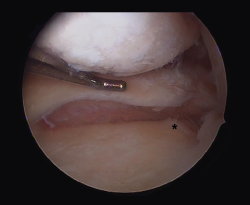

One of the aspects often not adequately taken into account when considering the surgical management of knee instability is the influence of the loading axes upon the instability itself. A varus morphotype or axis associated to anterior instability due to ACL deficit tends to be the most frequent combination.

[[{"fid":"4714","view_mode":"default","fields":{"format":"default","alignment":""},"type":"media","field_deltas":{"5":{"format":"default","alignment":""}},"link_text":null,"attributes":{"class":"media-element file-default","data-delta":"5"}}]]

Effect of varus deformity upon the anterior cruciate ligament

Different studies have shown that deformity of the coronal axis in varus considerably increases loading upon the ACL(40). Mechanical varus of 10º implies an overload of over 400% upon the ACL at 30º of knee flexion or 100% in extension. Minor deviations of the neutral mechanical axis, even slightly above "physiological" varus, such as 5º, already imply an increase in stress upon the ACL (250% at 30º and 68% in extension).

In addition, mention must be made of the high prevalence of meniscal damage associated to ACL lesions(41,42), due to simultaneous damage to both structures, or as a consequence of stress secondary to the instability. Therefore, the combination of varus and anterior instability defines a harmful pattern requiring the consideration of single-step resolution of both situations when marked varus is associated to anterior instability(43).

We should bear in mind that although the indication of osteotomy resides in varus correction (coronal plane), the osteotomy will also affect the sagittal and axial planes (Figure 5).